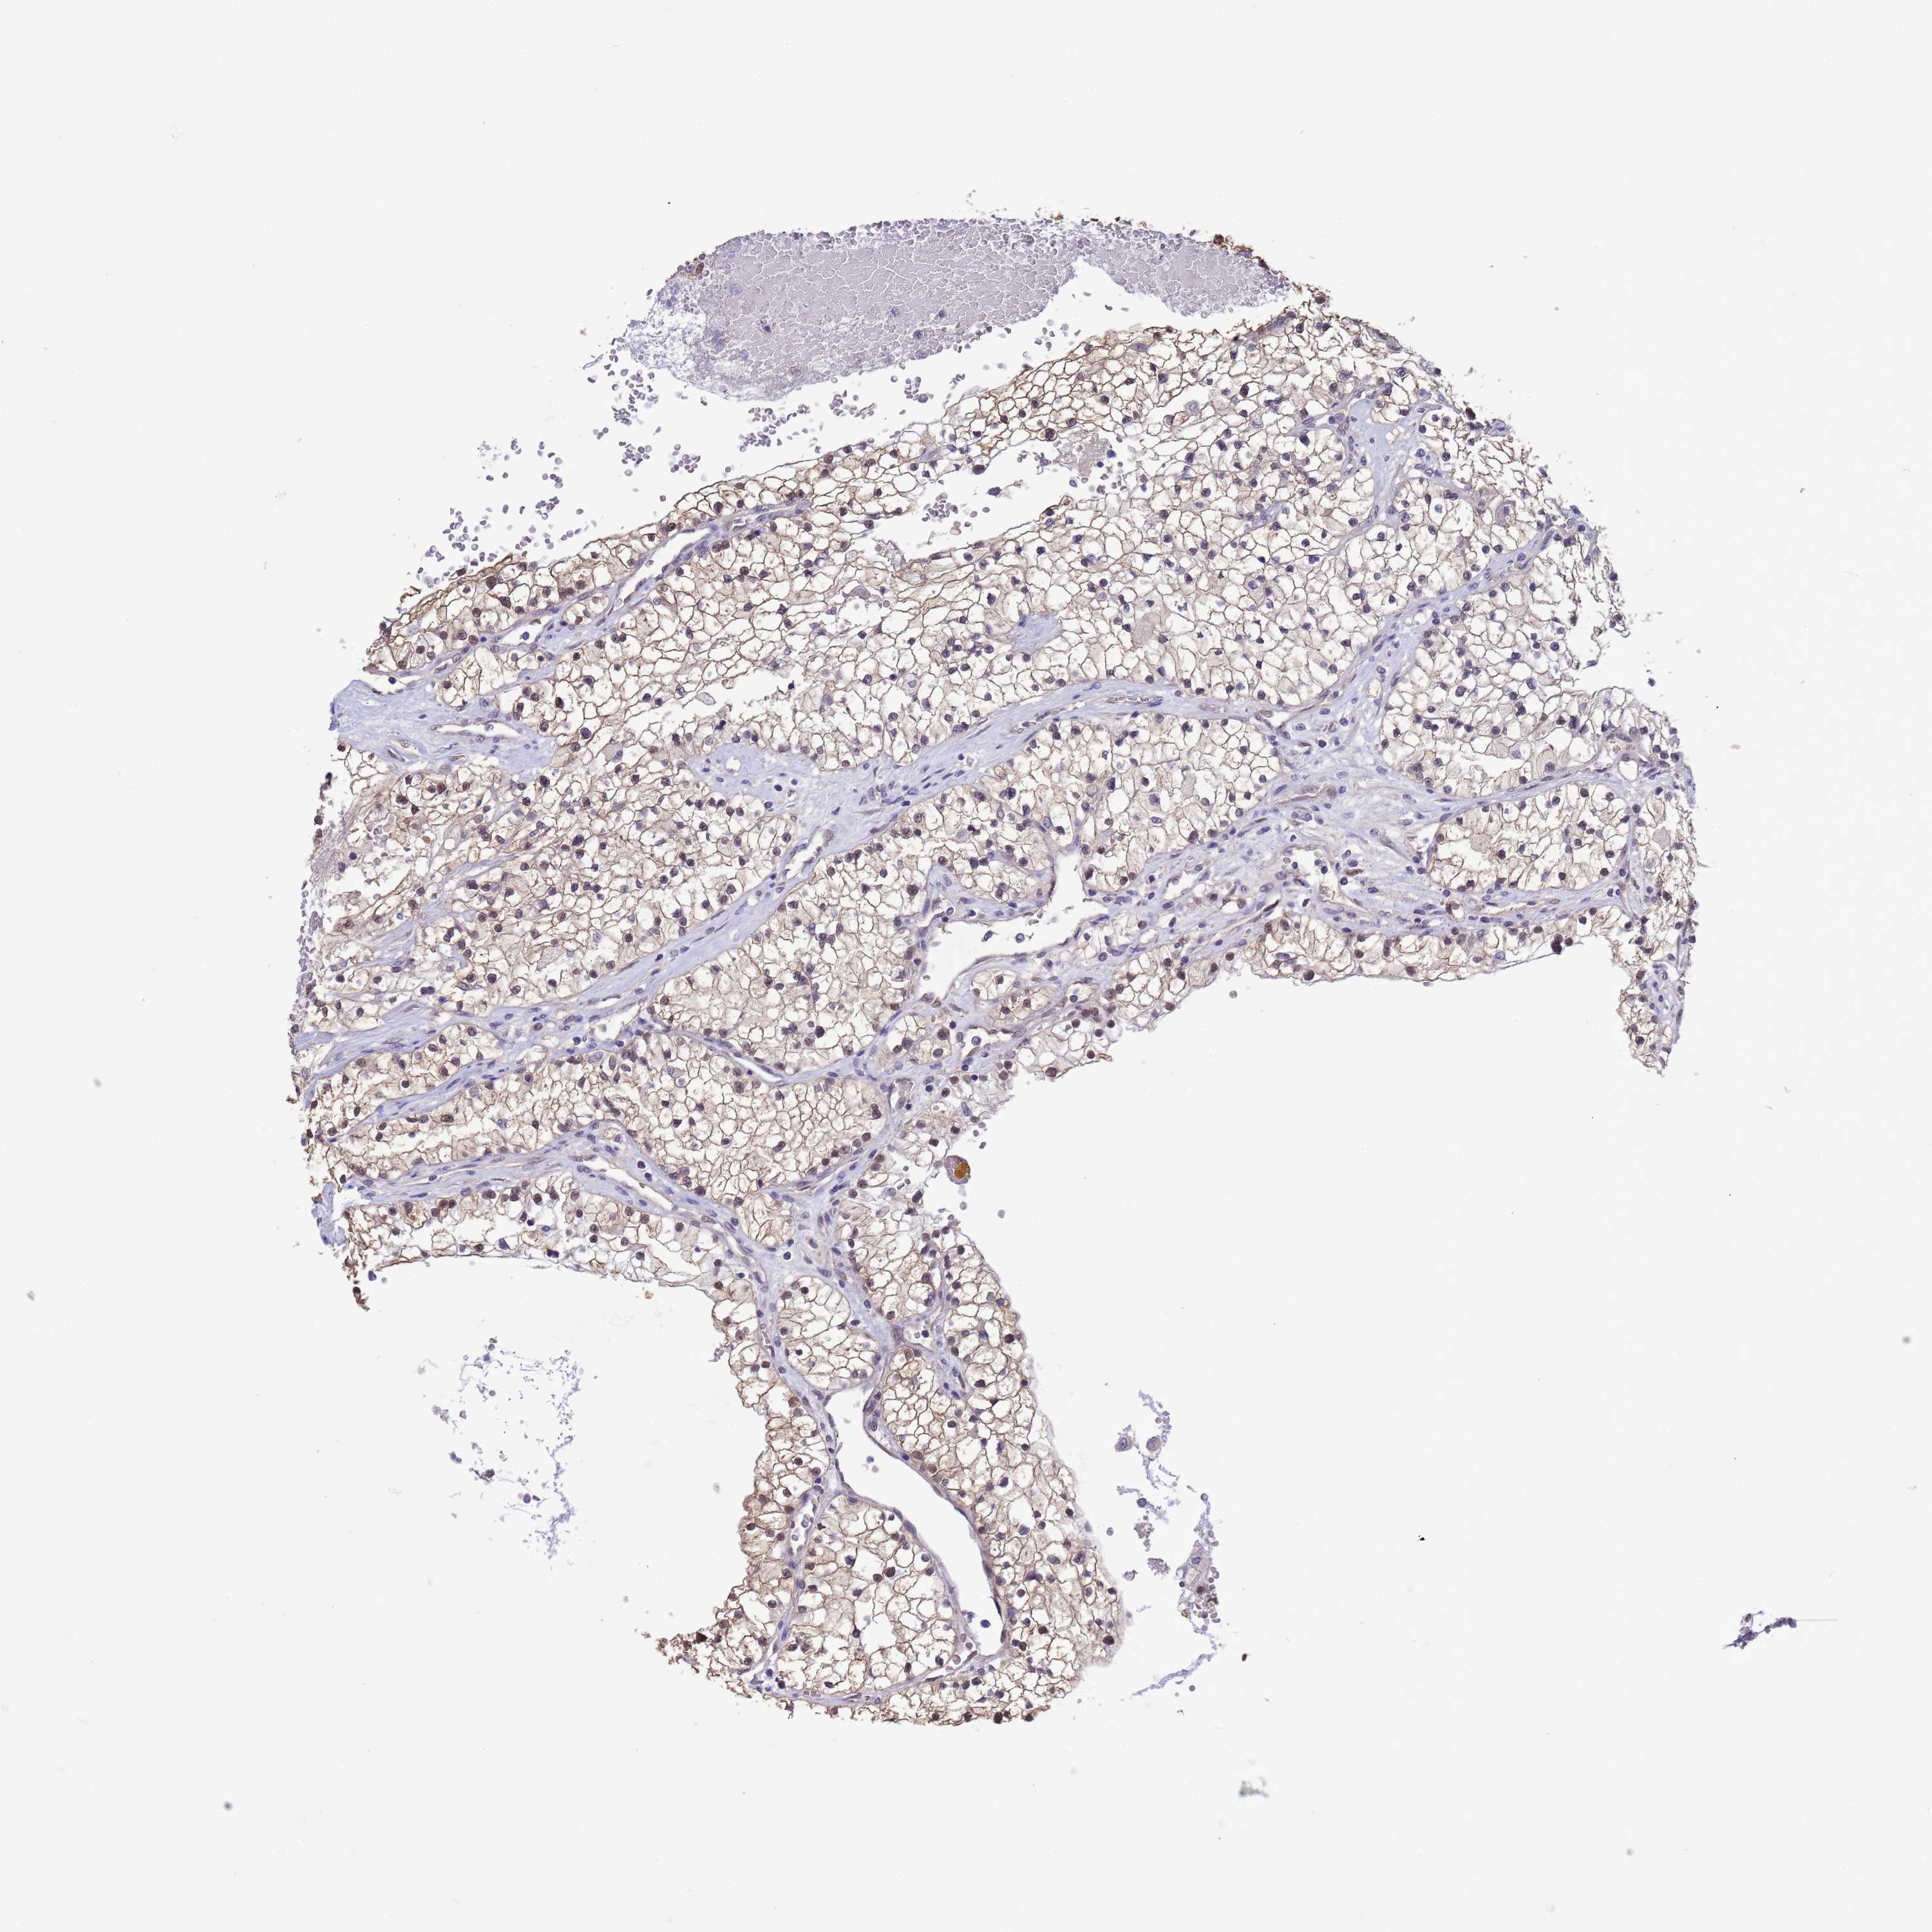

KIDNEY RENAL CLEAR CELL CARCINOMA (VALIDATION) - Interactive survival scatter ploti

The Survival Scatter plot shows the clinical status (i.e. dead or alive) for all individuals in the patient cohort, based on the same data that underlies the corresponding Kaplan-Meier plots. Patients that are alive at last time for follow-up are shown in blue and patients who have died during the study are shown in red.

The x-axis shows the expression levels (FPKM) of the investigated gene in the tumor tissue at the time of diagnosis. The y-axis shows the follow-up time after diagnosis (years). Both axes are complimented with kernel density curves demonstrating the data density over the axes. The top density plot shows the expression levels (FPKM) distribution among dead (red) and alive patients (blue). The right density plot shows the data density of the survived years of dead patients with high and low expression levels respectively, stratified using the cutoff indicated by the vertical dashed line through the Survival Scatter plot. This cutoff is automatically defined based on the FPKM cutoff that minimizes the p-score. The cutoff can be changed by dragging the vertical line or by entering a cutoff value in the square labeled "Current cut-off".

Under the Survival Scatter plot the p-score landscape (black curve; left axis) is shown together with dead median separation (red curve; right axis). Dead median separation is the difference in median mRNA expression between patients who have died with high and low expression, respectively. It is calculated as follows: median FPKM expression of dead patients with high expression - median FPKM expression of dead patients with low expression. This is intended to aid the user in visually exploring custom cutoffs and the associated p-scores and dead median separation.

Individual patient data is displayed and can be filtered by clicking on one or more of the category buttons on the top of the page. Categories describing expression level and patient information include: high, low, alive, dead, female, male and tumor stages. The scale of the x-axis can be toggled between linear and log-scale by clicking on the "x log" button. Mouse-over function shows TCGA ID, patient information and mRNA expression (FPKM) for each patient.

& Survival analysisi

Kaplan-Meier plots summarize results from analysis of correlation between mRNA expression level and patient survival. Patients were divided based on level of expression into one of the two groups "low" (under cut off) or "high" (over cut off). X-axis shows time for survival (years) and y-axis shows the probability of survival, where 1.0 corresponds to 100 percent.

ZNF461 is not prognostic in Kidney Renal Clear Cell Carcinoma (validation)

Best expression cut offi

: 3.79

P scorei

N/A

Average pTPM 3.9

Number of samples 100